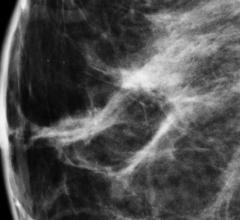

The women’s health channel includes news, videos, podcasts and other content related to technology used to detect and treat breast cancer and cervical cancer, including mammography, breast magnetic resonance imaging (MRI), automated breast ultrasound (ABUS), breast ultrasound, breast biopsy and breast radiation therapy.

Only one radiological modality – mammography – is used today for screening. Yet, as America hurdles toward preventive ...

Advances in digital mammography are evolving as clinicians look to improve breast cancer screening in women. In recent ...

Increasing research on women with dense breasts is having a positive effect on imaging modalities. It is estimated that ...